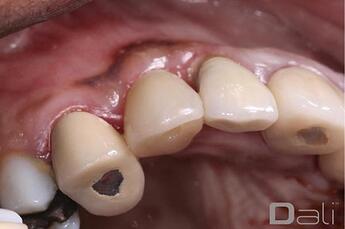

Initial Case Photos

Following a GBR at the time of implant placement, a buccal ridge deficiency persisted. Surgical uncovery of the implant to expose the cover screw revealed successful bone regeneration around the implant, but a residual lack of ridge contour. Instead of using a traditional particulate graft covered with a resorbable membrane, a “flexible bone graft” sheet, DALI Flex Graft, was placed over the buccal plate to augment the buccal contour. Because the graft comes hydrated, it is easy to handle and adapt to the defect location. The flap was then pulled over the graft and adapted around the healing abutment. Following 6 weeks of healing, we see nice healing and an obvious increase in the facial contour.